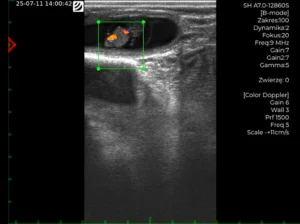

W YOUNG CATTLE RANCHERS INTERNSHIP PROGRAMME (PROGRAM STAŻU DLA MŁODYCH HODOWCÓW BYDŁA w Nigerii) zbadaliśmy tę rzeczywistość, używając wykrywacza rui dla krów Draminski S.A., który pomaga sprawdzić oporność elektryczną pochwy, która ulega zmianie w trakcie cyklu rujowego. To ostateczne narzędzie pomaga wyeliminować zgadywanie w sztucznej inseminacji bydła, a jednocześnie określa idealny czas na inseminację. To praktyczne doświadczenie uświadomiło nam kluczową rolę profilowania w przekształcaniu produktywności zwierząt gospodarskich.